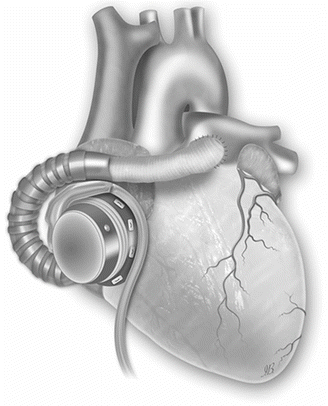

Fig. 31.5

Right ventricular support by cannulating the body of the right atrium (Picture by Ilaria Bondi’s Peppermint Advertising)